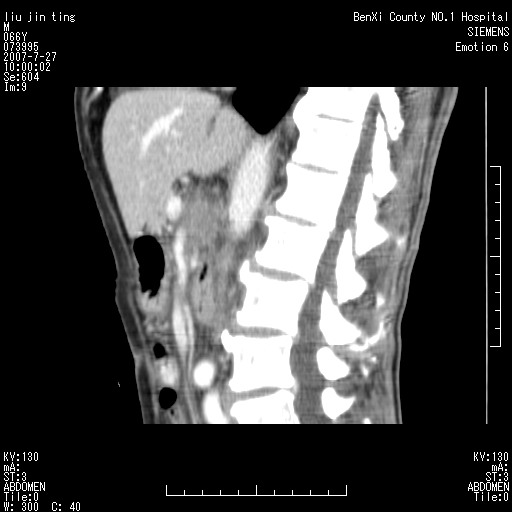

腹痛,背痛,无恶心呕吐,不黄,彩超示胰腺钩癌,ct扫描病灶平扫30-40hu,增强后动脉期40--60hu,静脉期50-68hu,真的是钩突上的么?您要试一试么?

动脉期

静脉期